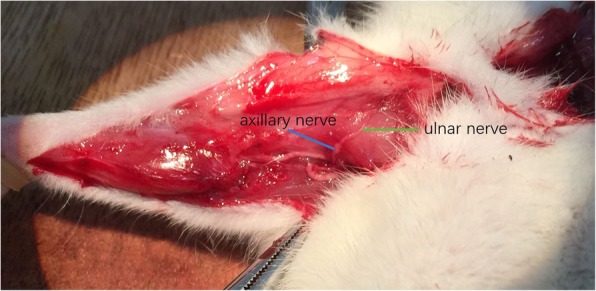

Group A (cC7 --- median nerve): A right longitudinal incision was made on the inner side of the upper arm. The ulnar and median nerves were identified near the retracing point of the ulnar nerve. (Fig. 1) Both of them were cut off. The proximal end of the ulnar nerve was sutured to the distal end of the median nerve without tension.

Fig. 1.

cC7 transfer to median nerve: The ulnar nerve and median nerve were identified at the turning point of ulnar nerve